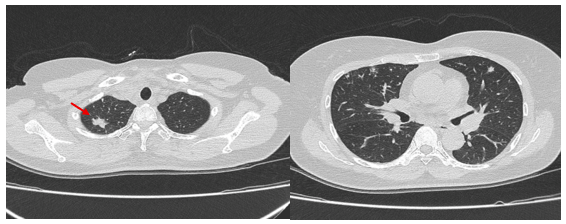

Hình 1.

Hình ảnh cắt lớp vi tính ngực có tiêm: thùy trên phổi (P) có nốt tổn thương kích thước 13x14mm, bờ không đều, ngấm thuốc, sau tiêm. Nghi ngờ tổn thương nguyên phát (mũi tên đỏ)

- Cắt lớp vi tính lồng ngực: Đám xẹp vùng đỉnh phổi phải, nốt đặc nhỏ kích thước 2-3mm. Không thấy hạch to hay khối trong trung thất

Hình 10: Hình ảnh cắt lớp vi tính ngực có tiêm: Đám xẹp vùng đỉnh phổi phải, nốt đặc nhỏ kích thước 2-3mm

Hình 11: Hình ảnh cắt lớp vi tính ngực có tiêm: Không thấy hạch to hay khối trong trung thất

Nhận xét: Chỉ sau 03 chu kỳ Pemetrexed – Carboplatin – Pembrolizumab, hình ảnh chụp cắt lớp vi tính cho thấy tổn thương phổi nguyên phát và các hạch giảm kích thước đáng kể. Đáp ứng điều trị được đánh giá là đáp ứng một phần theo tiêu chuẩn RECIST 1.1. Sau 9 chu Pemetrexed – Pembrolizumab, bệnh nhân tiếp tục ghi nhận cải thiện rõ rệt các triệu chứng lâm sàng, thể trạng ổn định, không xuất hiện tác dụng không mong muốn nghiêm trọng.Đánh giá trên hình ảnh chụp cắt lớp vi tính cho thấy tổn thương phổi nguyên phát tiếp tục giảm kích thước không ngấm thuốc chỉ còn là đám xơ xẹp vùng đỉnh phổi phải, các hạch trung thất và ngoại vi thu nhỏ rõ rệt, không phát hiện được trên phim chụp và không ghi nhận tổn thương di căn mới.